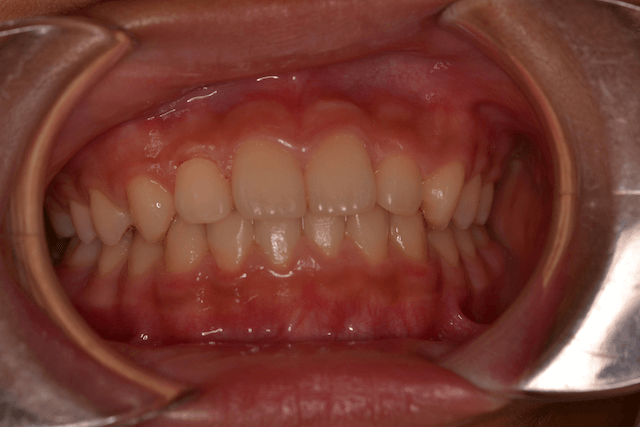

受け口(反対咬合・下顎前突)の症例

受け口(反対咬合・下顎前突)をリンガルアーチ、セクショナルDBSで改善した症例

10歳男性

前歯のかみ合わせ

リンガルアーチ、セクショナルDBS

3年5か月